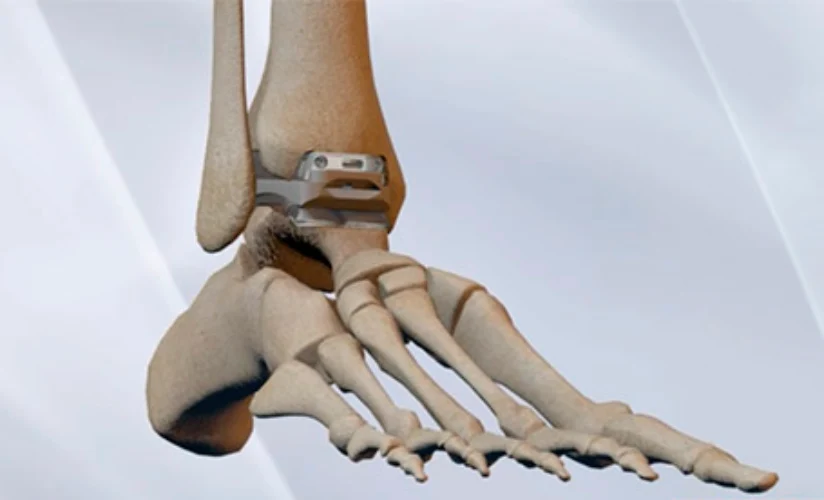

Prótesis de tobillo

Las prótesis de tobillo ya no son una innovación o un tratamiento experimental. A día de hoy, un tratamiento con resultados exitosos demostrados científicamente a corto y largo plazo. Por esta razón, se está considerando actualmente la implantación de una prótesis de tobillo como primera opción ante la existencia de patologías degenerativa del tobillo (artrosis), y no solo la artrodesis como hasta no hace mucho tiempo.

La fijación del tobillo o artrodesis es un tratamiento con buenos resultados en general, pero a expensas de eliminar una articulación tan importante como el tobillo y con secuelas demostradas a medio y largo plazo. Puede generar artrosis de otras articulaciones del pie, mayor gasto energético al caminar, cojera y afectación de la cadera o de la columna lumbar.